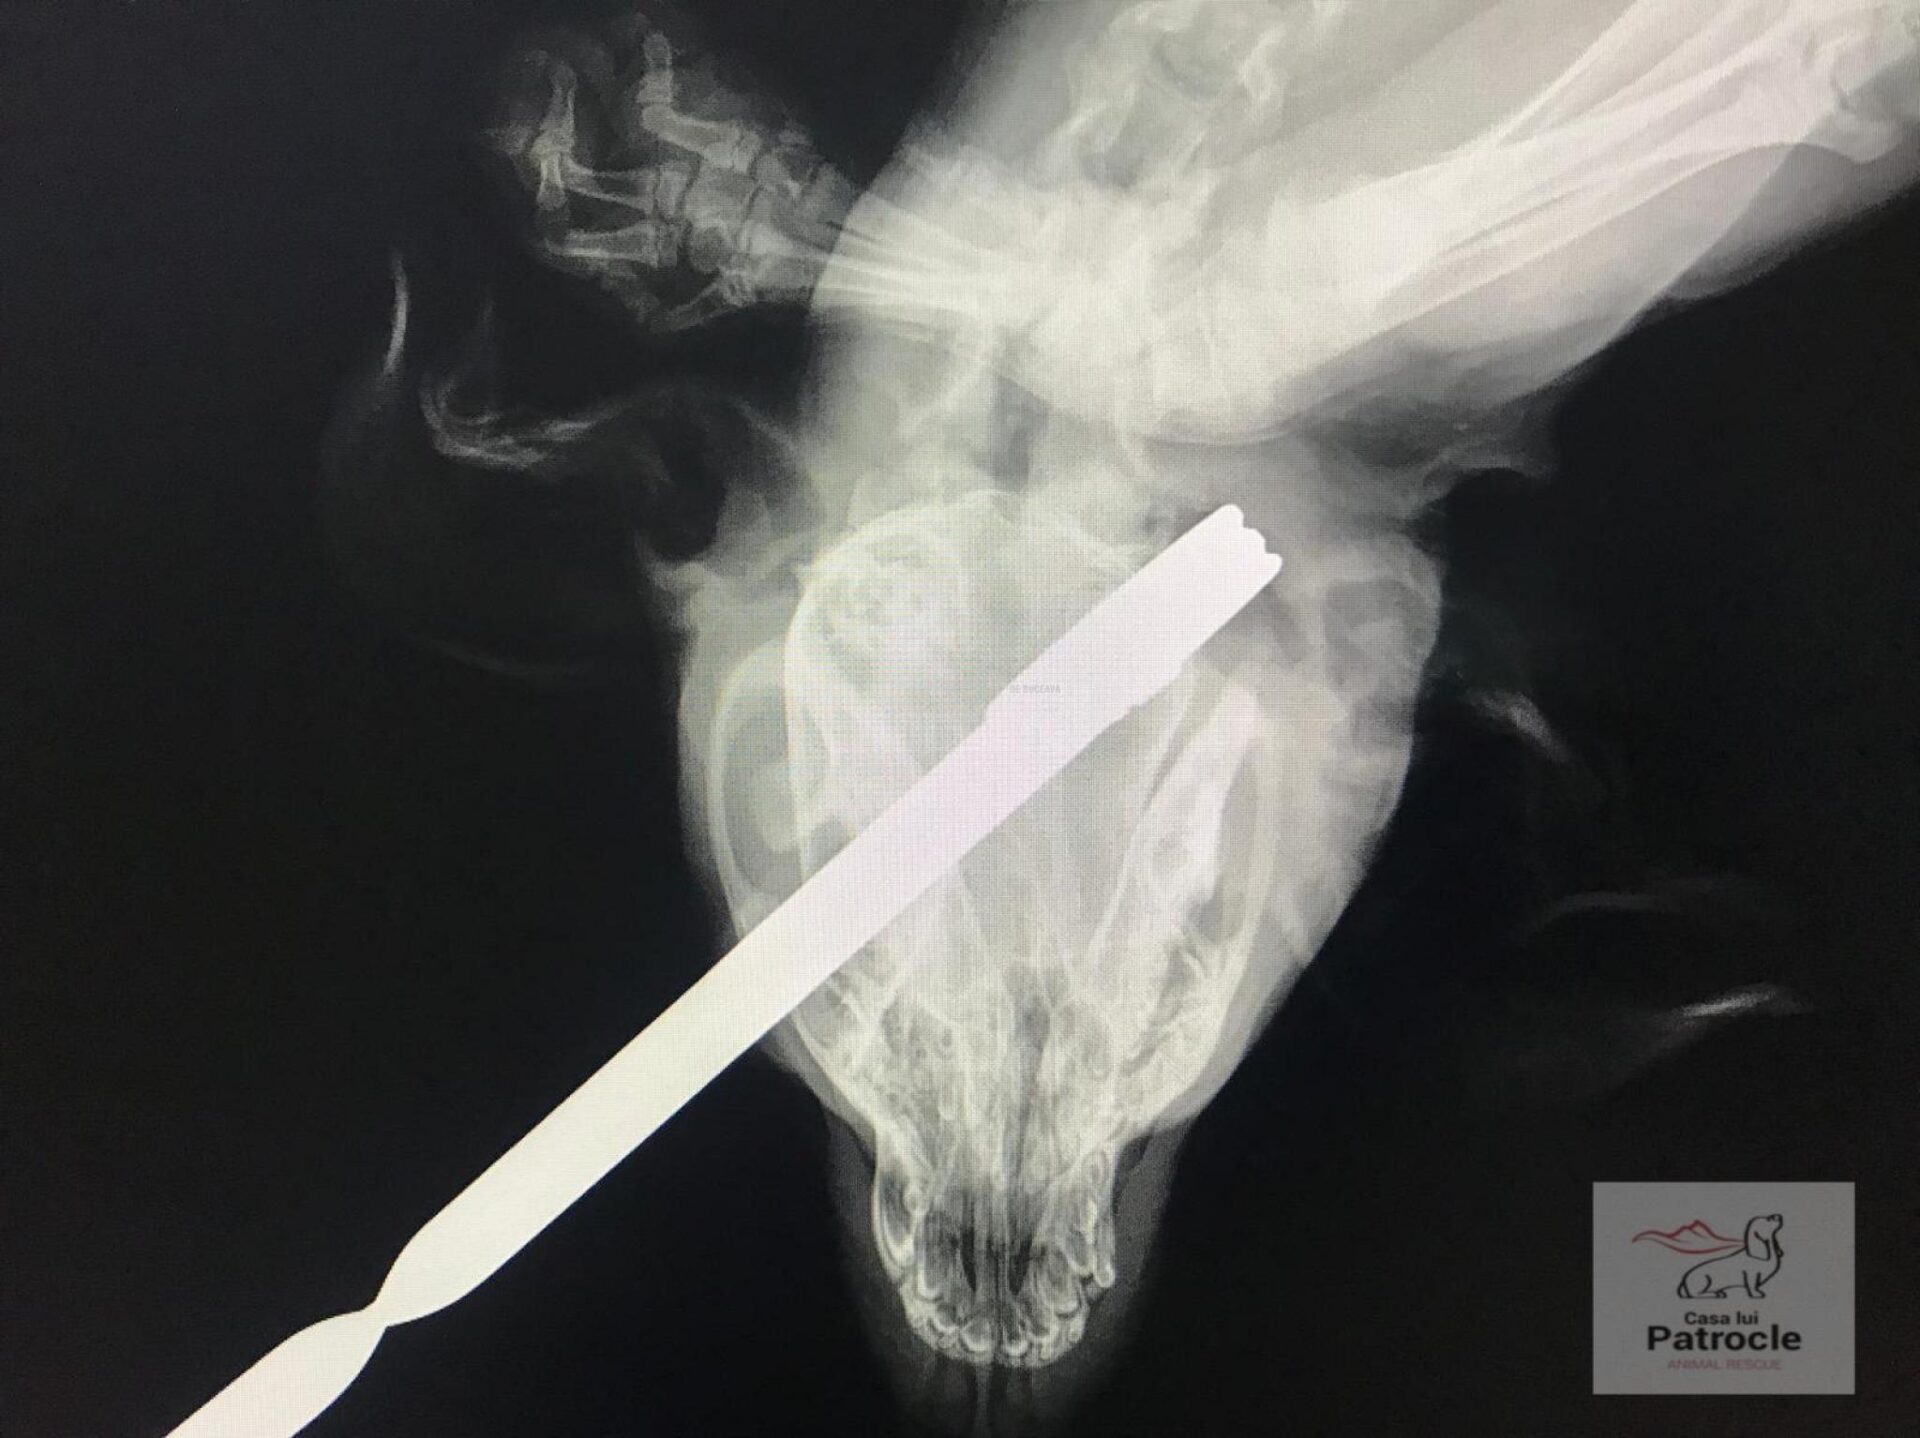

Asociația ”Casa lui Patrocle” a descoperit un caz șocant, care a părut a fi inițial un grav act de cruzime față de un animal, în satul Udești. În urma sesizării unei localnice, marți după-amiază, reprezentanții asociației au găsit în fața unei case un câine care avea băgat în el o bucată de fier forjat. Fierul era intrat prin gură, până în gât, bietul câine pierzând mult sânge și fiind găsit într-o stare deplorabilă.

S-a făcut expertiză criminalistică la fața locului, plecându-se de la bucata de fier din cavitatea bucală a câinelui. Polițiștii au găsit gardul cu decorațiuni similare, care aparține unui localnic în vârstă de 78 de ani. Acesta a declarat că puiul de câine a intrat în curte, s-a speriat de un câine mai mare, și în fuga disperată s-a înfipt în gard. Bătrânul a explicat cu lux de amănunte cum a găsit câinele în gard și cum a tăiat cu flexul bara, reușind să-l elibereze.

Câinele a ajuns la medicul veterinar Gabriel Gașpar, la Scooby Vet, care l-a operat și i-a scos bucata de fier din gât. După operație, câinele s-a trezit din anestezie, având șanse de recuperare.